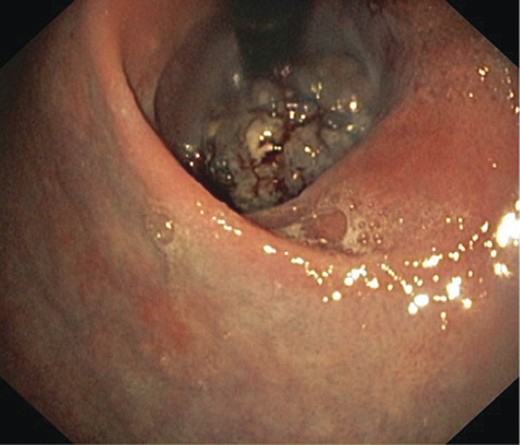

His initial endoscopy showed a 12 cm fungating, pigmented tumour occupying most of lower oesophageal lumen (Fig. 1). The biopsy was highly suggestive of primary malignant melanoma. Staging computed tomography (CT) and positron emission tomography (PET) showed extensive mediastinal, left supraclavicular and coeliac lymph node enlargement (FDG avid) with no evidence of metastatic disease (Fig. 2).

An endoscopic view of the fungating melanoma involving most of the oesophageal lumen.